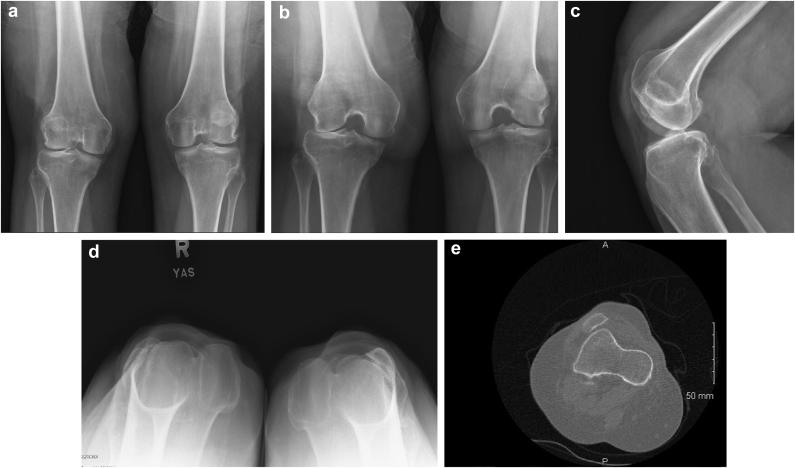

A 59-year-old woman with nail patella syndrome (NPS) presented with progressive and severe right knee pain for the past 3 years. Imaging demonstrated laterally dislocated patella, with asymmetric femoral trochlea, and advanced lateral compartment arthritis. The patient underwent robotic-assisted lateral unicompartmental knee arthroplasty (RAUKA). The patient saw marked improvements in patient-reported outcome measurements from her initial visit to the last follow-up visit. While treatment of knee osteoarthritis in patients with NPS can be difficult, especially with attempts of patellar realignment, we present a case of a patient who underwent RAUKA, with sustained improvements in patient outcomes and range of motion, at the 2-year follow-up visit. This study is the first of its kind to demonstrate the use of a novel technology in a rare condition.

一名59岁的指甲髌骨综合征(NPS)女性患者,在过去3年中出现进行性严重右膝疼痛。影像学检查显示髌骨外侧脱位,股骨滑车不对称,外侧间室关节炎进展。该患者接受了机器人辅助外侧单髁膝关节置换术(RAUKA)。从初次就诊到最后一次随访,患者报告的结局指标有显著改善。虽然NPS患者的膝骨关节炎治疗可能很困难,尤其是在尝试髌骨重新定位时,但我们介绍了一例接受RAUKA治疗的患者,在2年随访时患者结局和活动范围持续改善。本研究首次证明了在罕见疾病中使用新技术的情况。